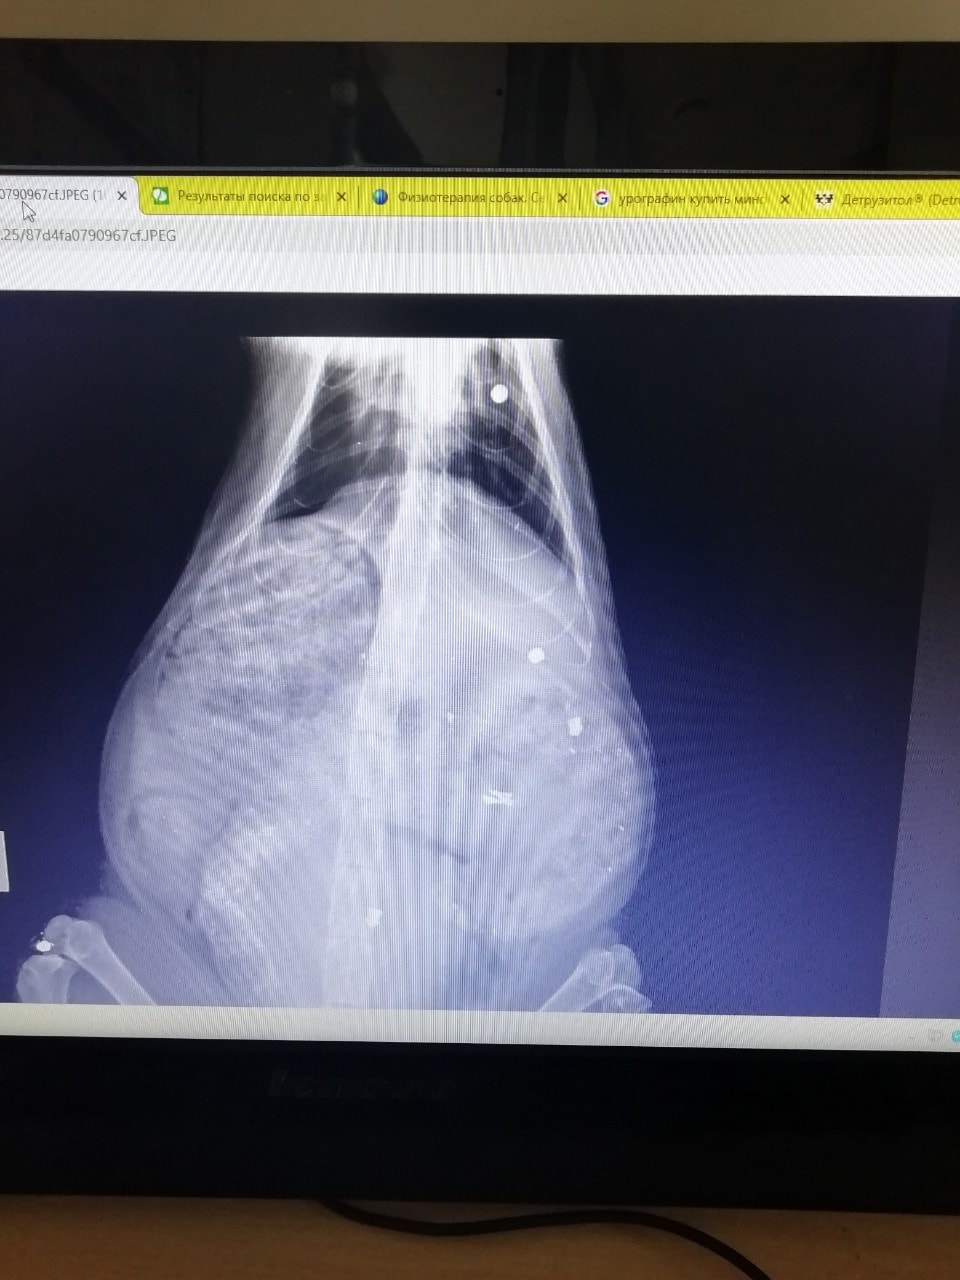

Сделали рентген и охнули.

Операцию делать не стали — кот не в том состоянии, чтобы ее просто пережить. Поставили катетер, чтобы он мог хотя бы облегчиться.